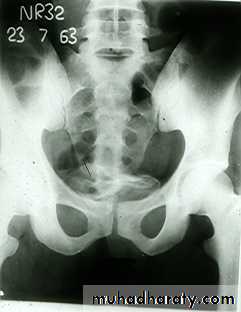

*Calcification is very common and important diagnostic findings. Very common in bladder ,less frequent in lower ureters ,but in advanced case involve the whole length of ureter .

*The appearance depends on degree of fullness of bladder ; thin linear opacity outlining bladder wall.

Empty bladder shows crowded linear opacities with calcified plaques.